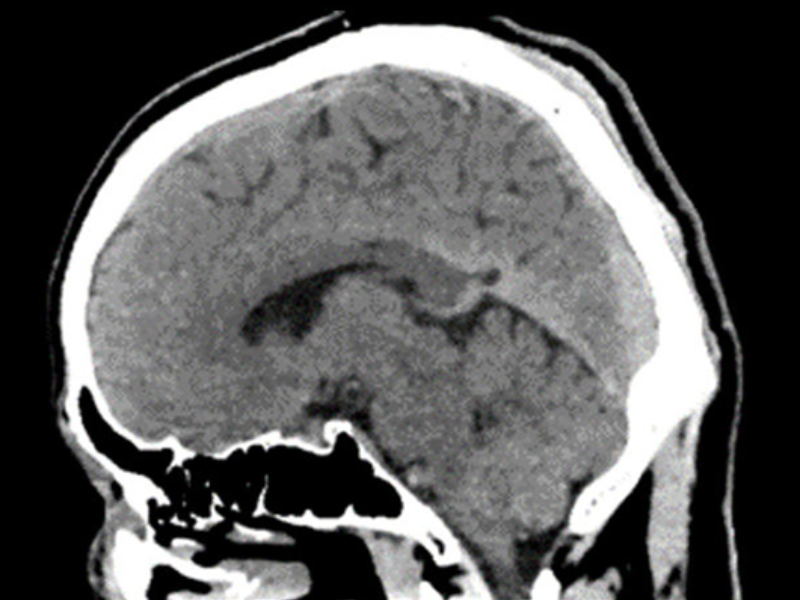

Half-Second Full Brain